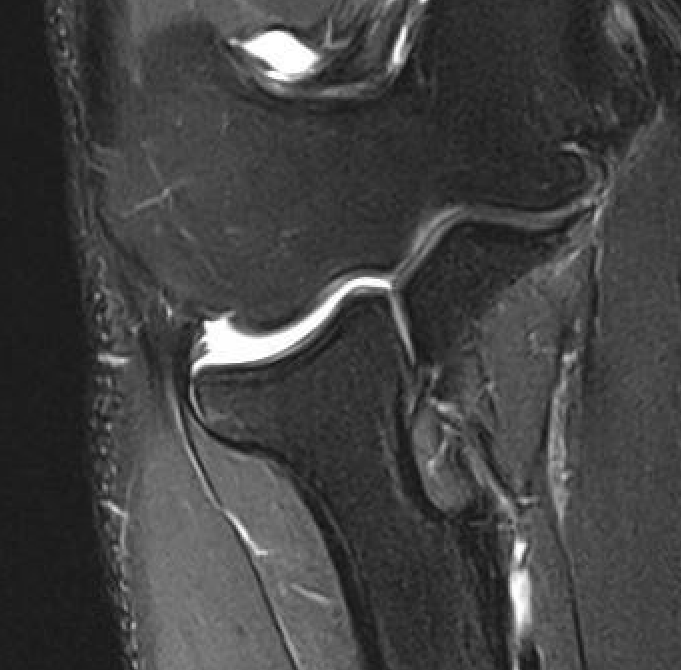

MRI

Normal

PRLI

Subtle instability of the radiocapitellar joint